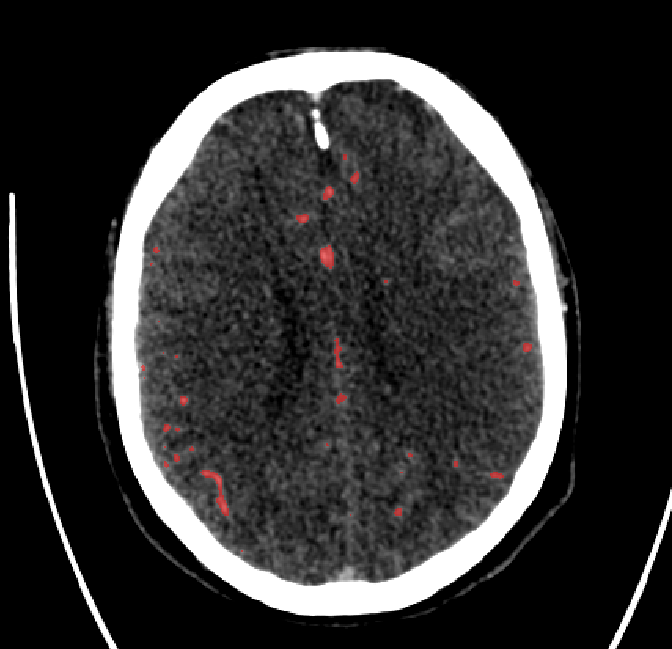

Qualitative Results

After fine-tuning, the two pre-train conditions appear to have little or no difference in terms of qualitative performance at the vessel segmentation task. However, when compared to the models trained only on real data, there are noticeable differences. Throughout Figures 4.3-4.9, the model pre-trained on scans with original CT noise is to be taken as representative of segmentation performed by the Perlin noise pre-training condition. Images showing the hand-labeled ground truth, as well as the unlabeled slice, are presented for comparison.

Figure 4.5: Segmentations on a central slice. Unaltered image (left). No pretrain model (mid-left). Fine-tuned model (mid-right). Hand-labeled ground truth (right).

Refer to caption

Figure 4.6: Segmentations on a central slice. Unaltered image (left). No pretrain model (mid-left). Fine-tuned model (mid-right). Hand-labeled ground truth (right).

For vessels in the center of the head, all model types appear to accurately segment vessels. In certain cases, the models appear to learn to correctly avoid segmenting pieces of bone that could, in terms of shape and contrast, easily be confused with large vessels. An example of this can be seen in the frontal section of Figure 4.6.

The models appear to have a hard time segmenting vessels close to the skull surface. The model trained exclusively on patient data appears to struggle far more for these types on conditions than the fine-tuned models. Figure 4.8 shows an example of the fine-tuneds model having close to no trouble segmenting vessels near the left side of the skull, while the baseline model suffers heavily from false negatives. To lesser degree, this effect can also be observed in the frontal lobe of Figure 4.9 In the other hand, Figure 4.7 presents an example of both models failing to segment vessels near the top of the skull.

In the other hand, it should be noted that fine-tuned models suffered from false positives more often than models with no pre-training. The fine-tuned models appeared to occasionally segment regions near the skull, which although similar in intensity to vessels, had no resemblance in terms of shape. Examples of this are seen in Figure 4.4 near the occipital bone and near the right temporal bone. Examples of oversegmentation were observed to happen commonly around the internal carotid arteries. This is likely due to the amount of contact surface between the artery and the surrounding bone. There was also a tendency for all model conditions to segment bone regions that were similar in shape to large vessels (Figures 4.3 and 4.4). Bone structures in such regions have similar pixel intensities to the arteries transporting contrast material, which could explain the source of confusion for a model.

To our surprise, the models were able to occasionlly segment the shape of the internal carotid arteries correctly despite no boundary being visible to the naked eye between the vessel wall and the surrounding bone structure. An example of this can be seen in the fine-tuned model in Figure 4.3.